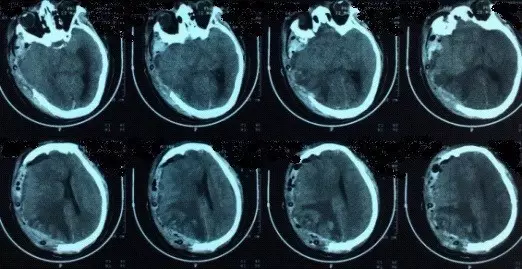

患者,男,40岁;因不明原因反复头痛并加重2月,于2017年4月21日当地医院头颅CT、MRI提示:双侧额颞顶部慢性硬膜下血肿收住院(图1)。并于4月24日行“左侧慢性硬膜下血肿钻孔引流术”。术后患者卧床、静脉补液,头痛症状有所缓解。复查头颅CT显示左侧血肿较前减少,但右侧稍增大(图2)。

但术后2天再次出现头痛,不能缓解,5月2日复查头颅MRI提示硬膜下血肿术后复发,伴小脑下坠,脑沟及小脑上方仍可见较多脑脊液,四脑室变小,颅内静脉系统扩张明显(箭头所示见横窦扩张)(图3)。

图2. 左侧慢性硬膜下血肿钻孔引流术后1天复查头颅CT,显示左侧硬膜下血肿较术前减少。

图3. 术后1周(5月2日)复查头颅MRI显示左侧硬膜下血肿术后复发,伴小脑下坠,脑沟及小脑上方仍可见较多脑脊液,四脑室变小,颅内静脉系统扩张明显(箭头所示见横窦扩张)。